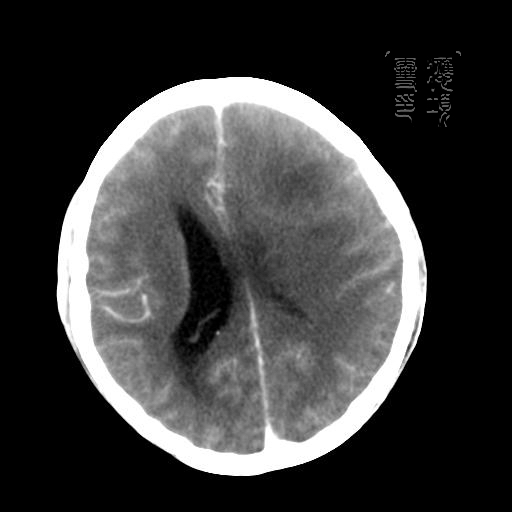

m 52y

二月前癫痫入院, 无既往史,现头痛、呕吐、视力减退、复视行ct平扫及增强检查。

见环形,结节样强化,考虑囊性星型细胞瘤。

左额叶囊实性占位,以囊性为主,并见明显强化不规则壁结节,占位效应明显,首先考虑是囊性星形细胞瘤.

环形强化,壁薄、完整、光滑,而且有结节强化,个人考虑不典型脑脓肿多!